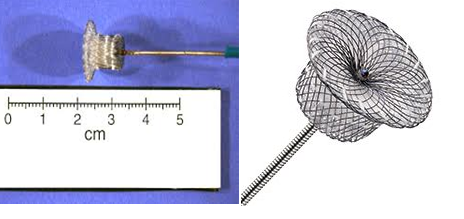

- TAVR as treatment of choice in severe aortic regurgitation with multivalve pathology and chronic kidney disease patientHeart valvular diseases